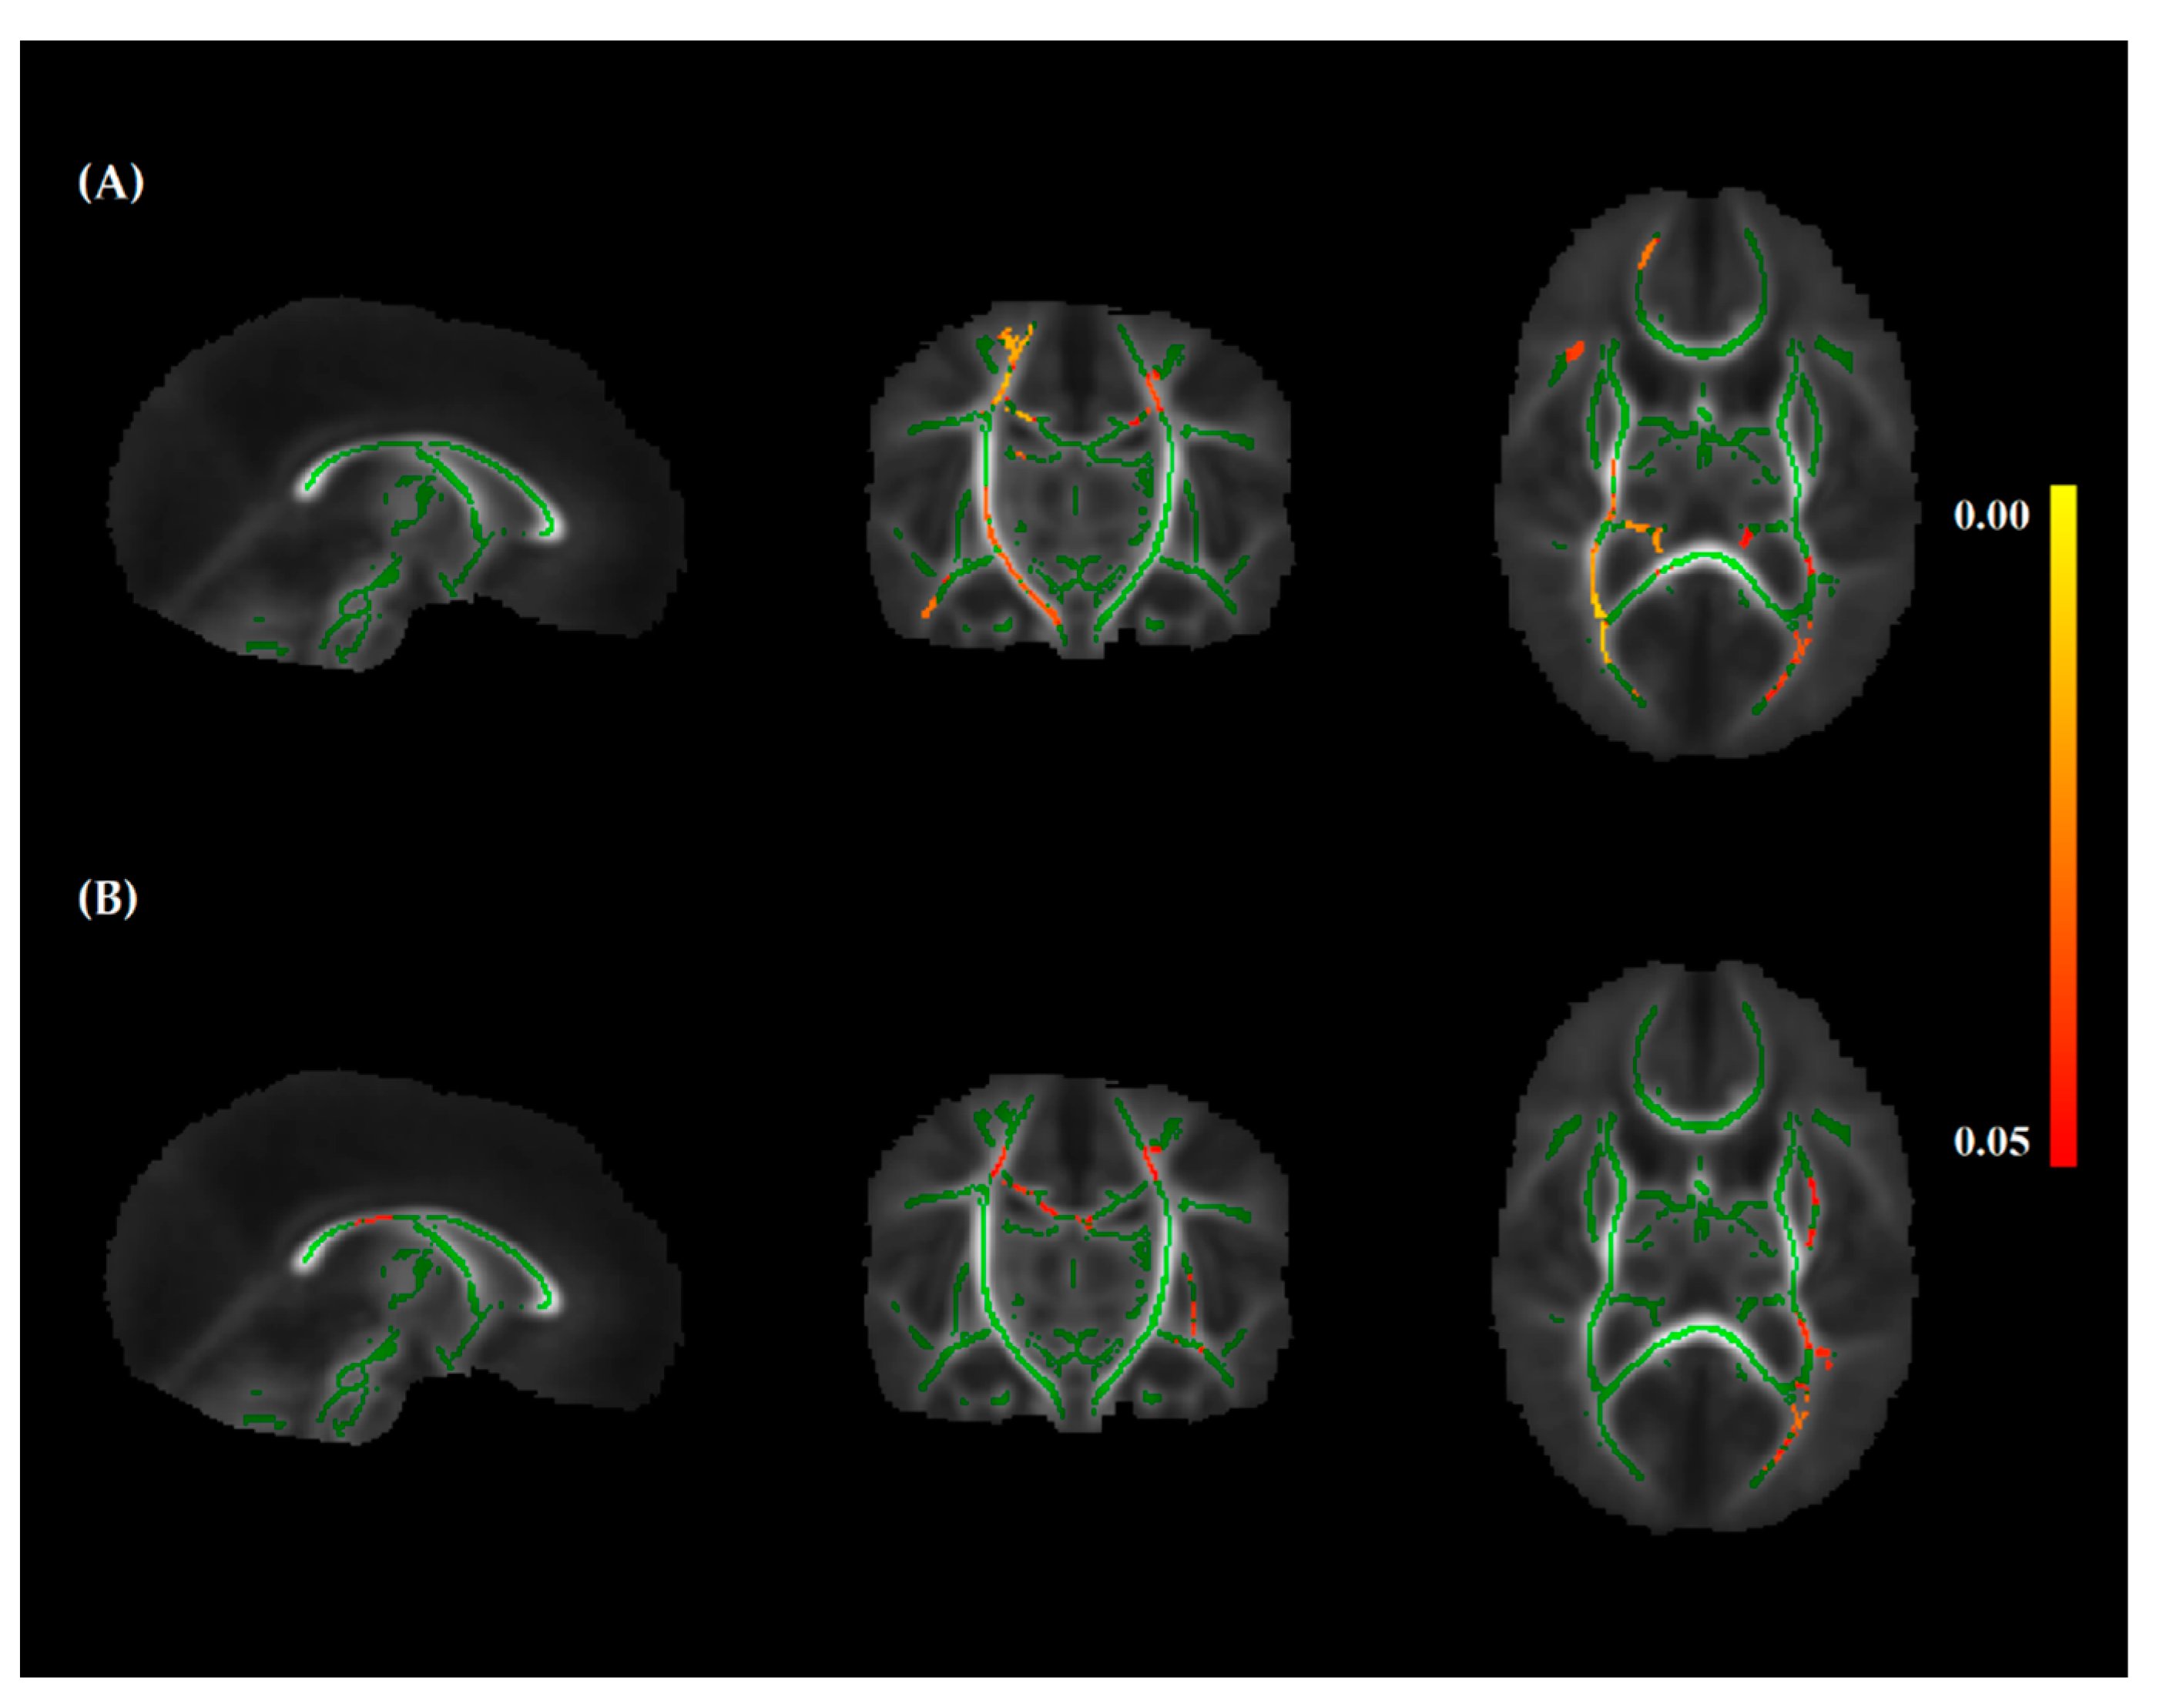

3.3. Nutritional Intake and White Matter Integrity

4.1. Protein Intake and White Matter Integrity